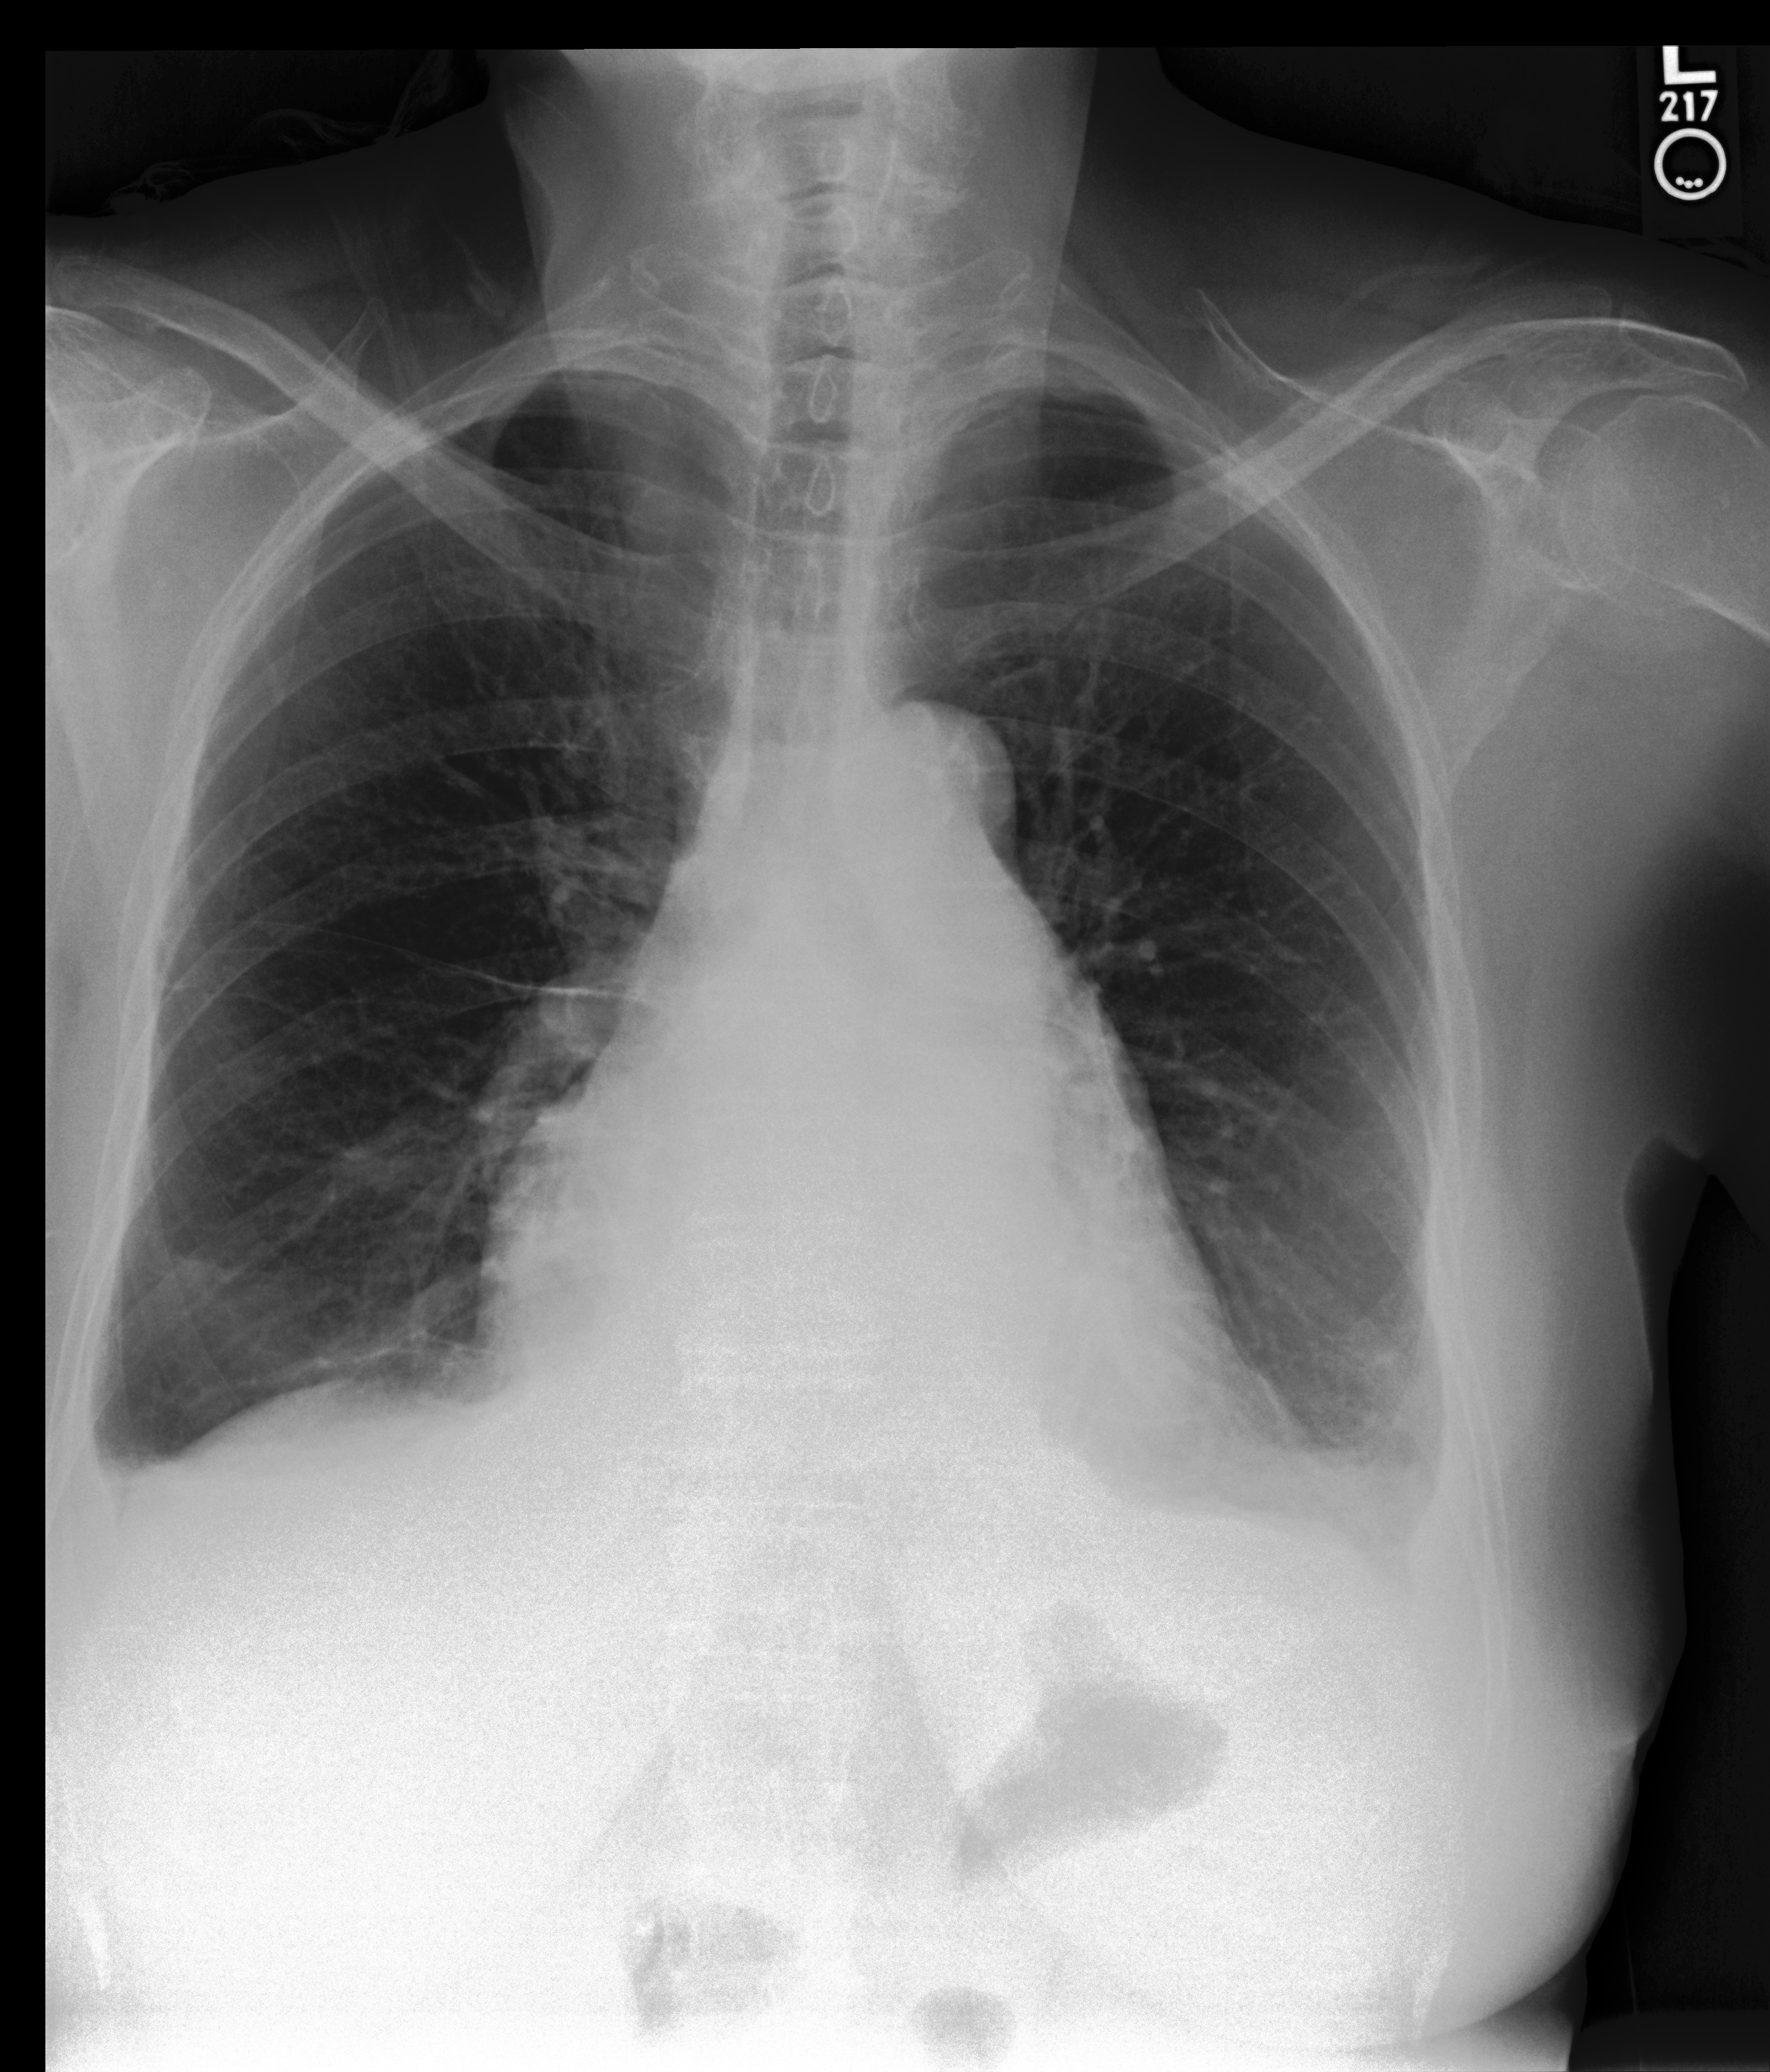

We additionally provided our model performance illustrations in Table 2 containing the original X-Ray images from the MIMIC-CXR dataset, the ground truth expert label and the model prediction (SAT + GPT-3). We manually underlined the similarities and identical diagnoses in texts to guide the eye.

Chest X-Ray Ground Truth Our predictions

[Uncaptioned image] 1. Stable bilateral small pleural effusions and atelectasis. 2. Enlarged pulmonary artery, suggesting pulmonary hypertension. No significant interval change. Bilateral small pleural effusions and adjacent atelectasis are overall unchanged. The heart is top-normal in size, unchanged. The pulmonary artery is enlarged, suggesting pulmonary hypertension. No demand, focal consolidation to suggest pneumonia, or pneumothorax. pleural effusion present. lung opacity present. no edema. cardiomegaly present. atelectasis present. as compared to previous radiograph, there is an increase in extent of a pre existing small left pleural effusion with subsequent atelectasis at left lung bases. otherwise, radiograph is unchanged. moderate cardiomegaly. mild fluid overload no overt pulmonary edema. no new focal parenchymal opacities suggesting pneumonia. unchanged position of right pectoral port a cath.